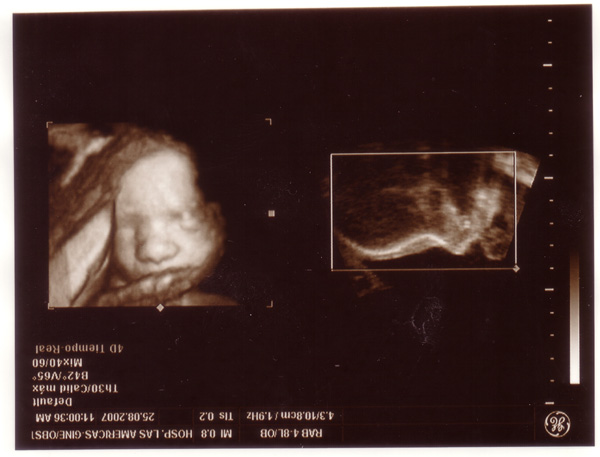

Hatalmas gratula! Nagyon szép kiscsaj! szépen látszik a pofija, s az öt ujja is